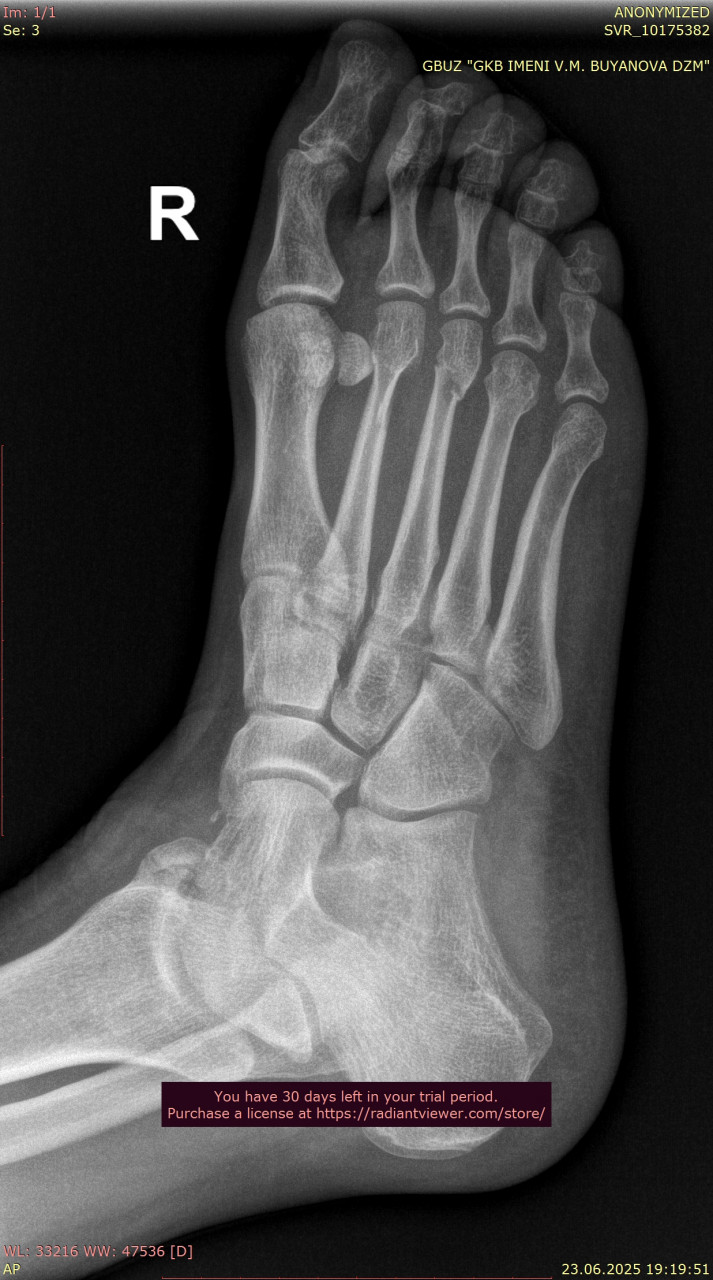

Андрей Павлович, Большое Спасибо Вам за ответ! Прикрепляю недостающий снимок стопы от 23.06.2025, когда был перелом, и снимки лодыжки от 25.08.2025, вчерашние, здесь тоже лимит файлов, снимки лодыжки от даты перелома могу прикрепить в следующем комментарии, и если Вас не затруднит, подскажите, пожалуйста, сильный ли у меня артроз суставов для возраста 38 лет?

Сравнивая ваши снимки от 23.06 и 25.08:

- Линии переломов на костях стопы и области голеностопного сустава больше не прослеживаются чётко, видна формирующаяся костная мозоль – это признак заживления.

- Смещения отломков нет, контуры выровнены, что говорит о правильном срастании.

- Для срока 2 месяца после перелома динамика положительная, основные признаки консолидации присутствуют. Обычно к этому времени разрешают постепенную нагрузку, но полное снятие опоры (ходьба без костылей, тростей) должно быть постепенным и согласовано с вашим травматологом.

По поводу артроза, на рентгене действительно заметны начальные изменения в суставах стопы (сужение суставных щелей, небольшие краевые разрастания), но они умеренные и для 38 лет не критичны. Такие изменения часто встречаются после травм и нагрузок, но выраженного деформирующего артроза нет.